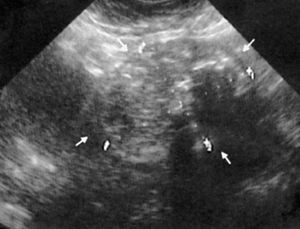

En el estudio ecográfico realizado por su ginecólogo se observa una masa pelviana de gran tamaño, con múltiples focos hiperecogénicos con sombra posterior sugestiva de mioma uterino probablemente calcificado (fig. 2).

Fig. 2.--Ecografía pelviana. Masa heterogénea de gran tamaño (flechas) con áreas hiperecogénicas con sombra posterior, sugestivas de calcificaciones.